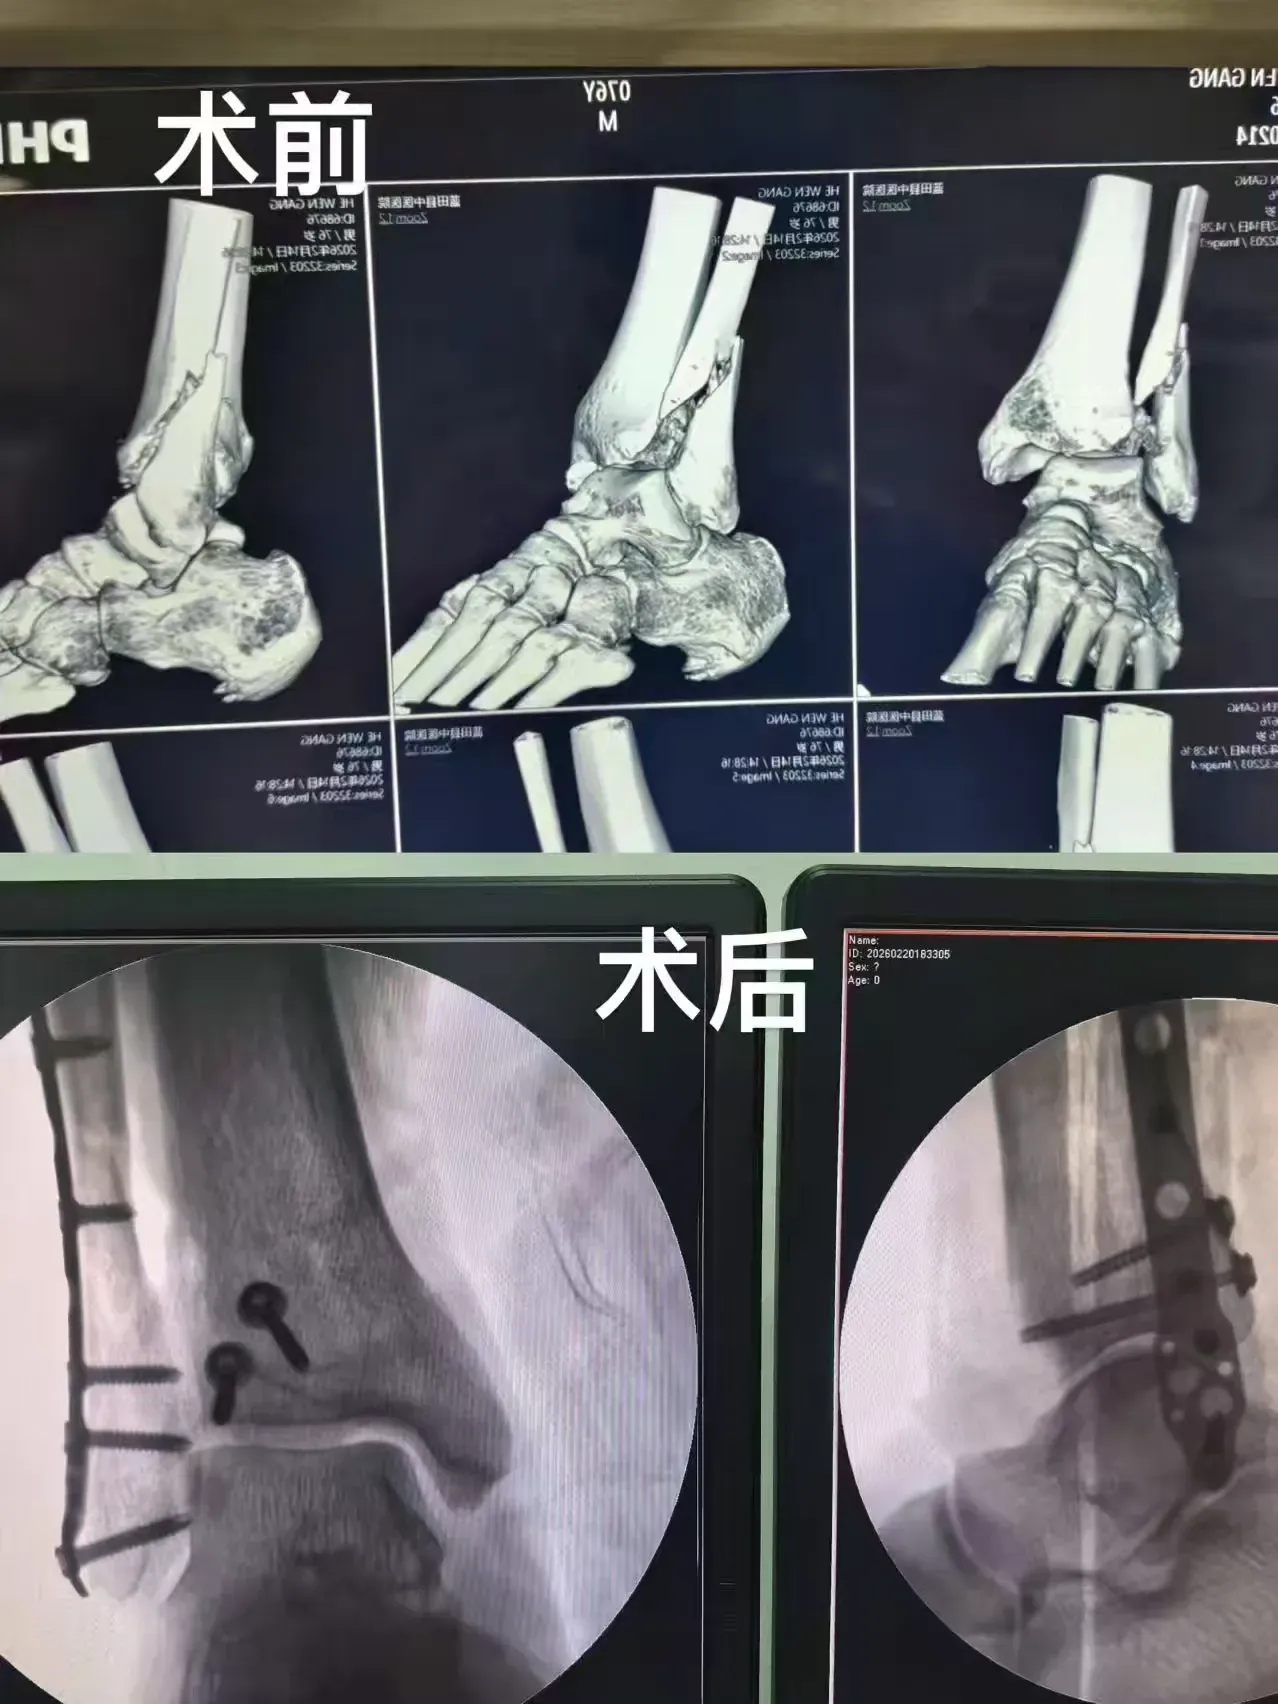

年味未散,守護(hù)不止。大年初四,手麻科再次迎來(lái)急診手術(shù)——一位骨折患者需要實(shí)施內(nèi)固定手術(shù)。面對(duì)手術(shù)需求,醫(yī)護(hù)人員毫無(wú)懈怠,迅速做好術(shù)前準(zhǔn)備,術(shù)中精準(zhǔn)配合、嚴(yán)謹(jǐn)操作,全力保障手術(shù)順利完成。術(shù)后轉(zhuǎn)運(yùn)過(guò)程中,因患者行動(dòng)不便,值班大夫主動(dòng)上前,與醫(yī)護(hù)人員一起小心抬送病人,動(dòng)作輕柔、呵護(hù)備至,用最樸實(shí)的舉動(dòng),傳遞著最溫暖的醫(yī)者溫情。沒(méi)有豪言壯語(yǔ),只有默默付出;沒(méi)有節(jié)日休憩,只有全程堅(jiān)守,他們用肩膀扛起的不僅是患者,更是沉甸甸的責(zé)任與信任。